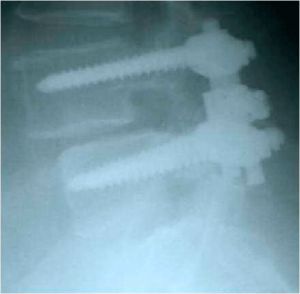

При контрольной рентгенограмме отмечено правильное положение транспедикулярной системы на уровне L4-L5 позвонков. (Рис.9a,b).

| Рис. 9 a,b. Ренгенограмма поясничного отдела позвоночника в боковой (a) и прямой (b) проекции. Транспедикулярная фиксация L4-L5 позвонков титановой конструкцией, удалена дужка L4 позвонка. |